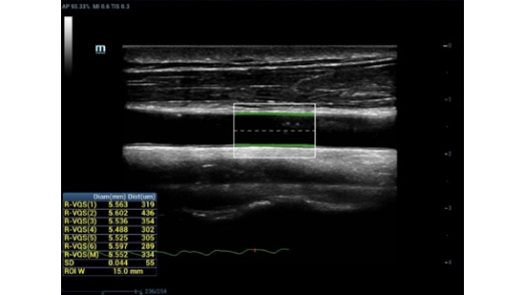

Dedicated and professional solutions